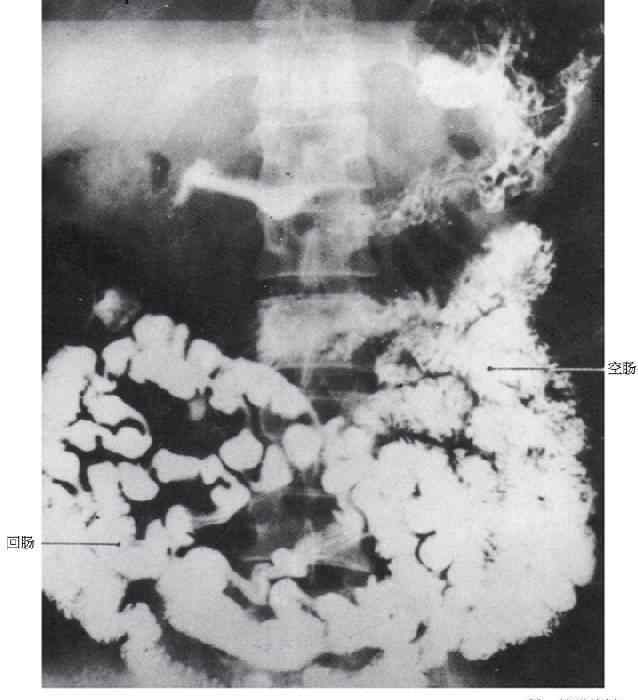

8小肠小肠

1空肠空肠,2回肠与空肠回肠交界处及空肠交界处,3回肠回肠,4盲肠盲肠,5附录